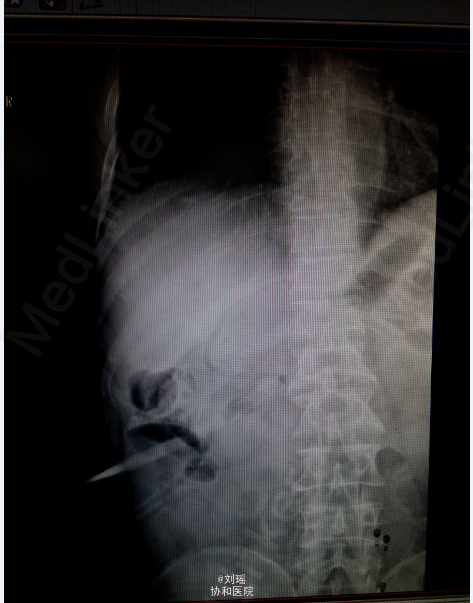

查体:生命体征平稳,慢性病容,皮肤巩膜重度黄染,右上腹T管,余无特殊。 辅助检查: 肝胆脾CT:右肾囊肿;胆总管粘液腺癌术后 T管造影:胆总管全段可见不同程度,不同大小之充盈缺损并不同程度狭窄,考虑为占位性病变。肝内胆管明显扩张。